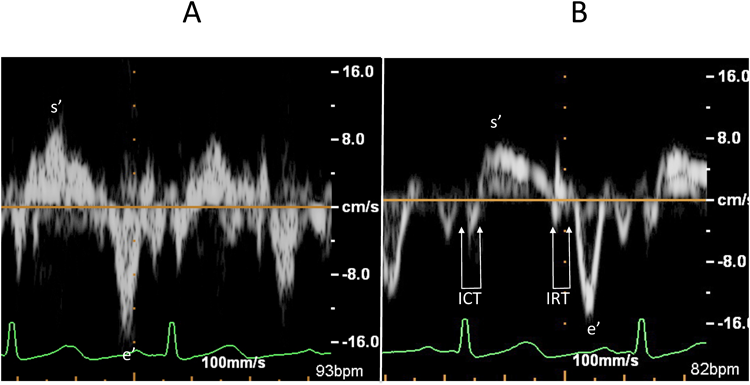

弁輪部は,収縮期に心尖部へ移動し(s′波),拡張期には拡張早期と心房収縮期に2峰性に心基部側へ移動する(e′波およびa′波).a′波とs′波の間には2相性の小さな波形を認め,等容性収縮期(isovolumic contraction time: ICT)に相当する.また,s′波とe′波の間にも2相性の波形を認め,等容性拡張期(isovolumic relaxation time: IRT)にあたる(Fig. 1).

ここで,解析に適した記録を得るためのコツについて触れたい.まず弁輪の運動方向とドプラカーソルはできるだけ平行に設定する.また,良好なドプラ波形を検出できるように,サンプルボリューム幅はやや広めとする(著者は学童で5~6 mmにしている).ドプラゲインは可及的に下げスペクトル包絡線(envelop)が認識できる記録が望ましい.ゲインを上げすぎるとノイズを拾い運動速度を過大評価するばかりでなく,時相解析が困難になるからである.最後に,低速の運動速度を記録するためドプラフィルターは可及的に低く設定する(Fig. 2).

Pediatric Cardiology and Cardiac Surgery 32(2): 70-77 (2016)

Fig. 2 Inadequate and adequate recordings of tissue Doppler imaging

The sample volume is placed on the lateral mitral valve annulus. A: Inadequate recording. Because of excess Doppler gain, the maximal velocity boundary of the spectral envelope is unclear. The vertical lineal Doppler artifacts lead to overestimation of each velocity. B: Adequate recording. After adjustment of the Doppler gain, the spectral envelope in the Doppler recording is clearly recognized. ICT and IRT can be easily measured. s′=systolic wall motion velocity; e′=early diastolic wall motion velocity; ICT=isovolumic contraction time; IRT=isovolumic relaxation time.